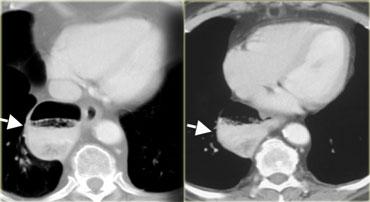

Bên trái là một bệnh nhân khác bị achalasia.

TRÁI: Thực quản giãn (mũi tên) được chiếu phía sau nhĩ phải. GIỮA và PHẢI: Hẹp thuôn nhẵn ngay trên cơ hoành (mũi tên).

Trong quá trình soi huỳnh quang, quan sát thấy một số nhu động với hình ảnh hẹp thuôn nhẵn điển hình ngay trên cơ hoành (mũi tên).